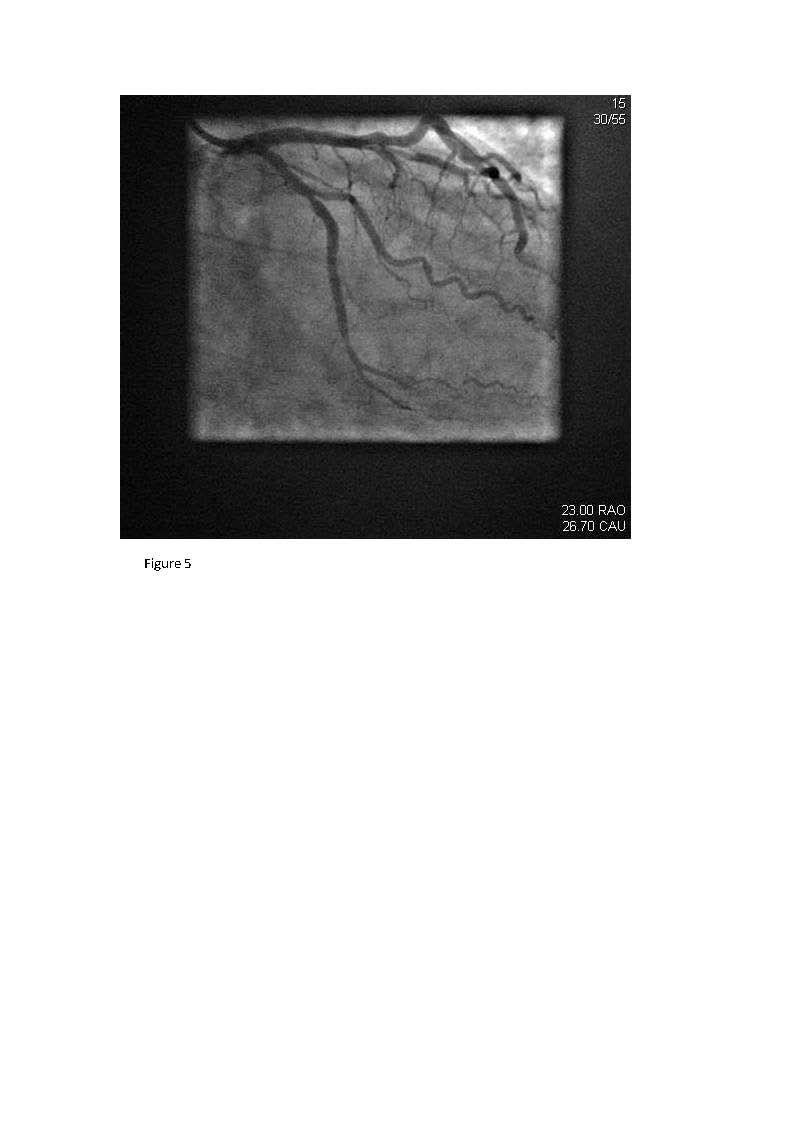

We report the case of a 50-year-old man with history of hypertension who presented with chest pain and subtle electrocardiographic (ECG) abnormalities. Only with the aid of additional high lateral and posterior ECG leads (V7-9) was a posterolateral acute myocardial infarction identified and subsequently confirmed with positive cardiac enzyme serology. Coronary angiography showed total occlusion of the left circumflex coronary artery, which was successfully recanalized via coronary angioplasty and stenting. This case highlights the use of high lateral and posterior ECG leads (15-lead ECG) in enhancing the diagnostic yield of a conventional ECG in patients presenting with symptoms suspicious for an acute coronary syndrome by disclosing a posterior myocardial infarction and guiding reperfusion therapy.